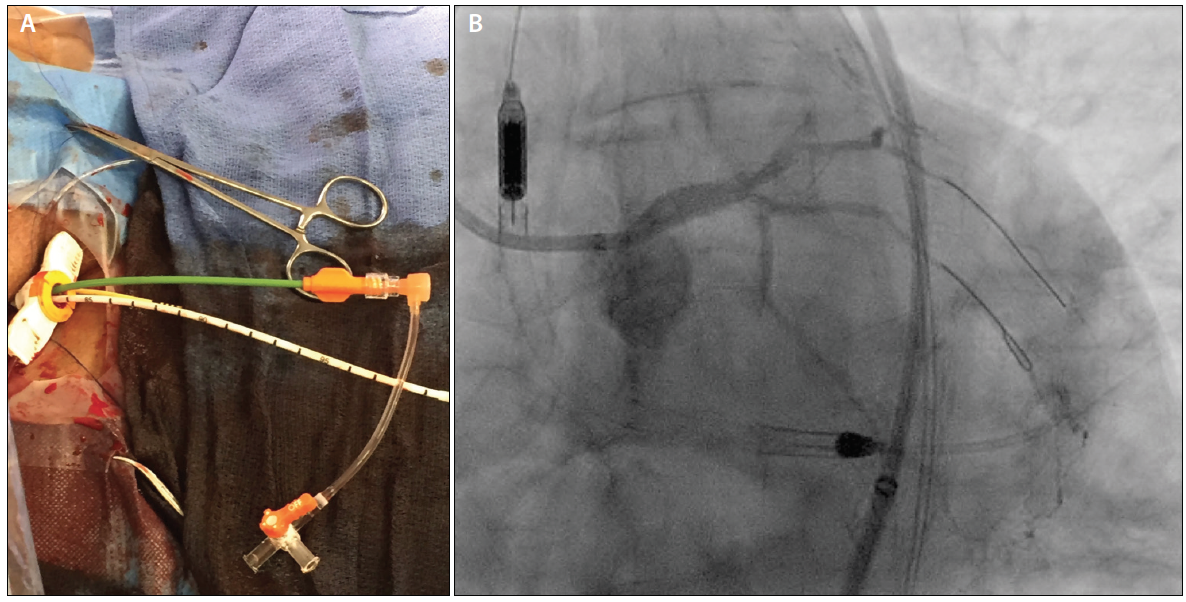

We achieved 7-F access to the left radial artery and right CFA. A combination of a 7-F LIMA guiding catheter and a 6-F TrapLiner catheter (Teleflex) was used to intubate the LIMA graft from the left radial approach. From the right CFA, a Glidewire Advantage guidewire (Terumo Interventional Systems) was carefully manipulated across the aortic lesion, along which a 10- X 40-mm predilation balloon was advanced. This balloon was inflated at 4 atm for 30 seconds, successfully predilating the aortic lesion. Next, the guidewire was exchanged for a Supra Core wire (Abbott) through a diagnostic catheter, and the right common femoral arteriotomy was sequentially dilated to allow placement of the 14-F Impella CP sheath. Thereafter, the Impella CP catheter was deployed to the left ventricle, and the patient was placed on circulatory support. Next, using the Impella single-access technique (Figure 3A)—recently publicized across many educational forums—a separate micropuncture access was created in the hub of the Impella placement sheath, a 7-F Destination sheath was placed in the abdominal aorta, and a 7-F guide catheter was used to intubate the LMCA.

Figure 3. The Impella single-access technique (A). After placement of the 14-F Impella CP sheath, a micropuncture needle was used to puncture the hemostatic membrane near one of the four corners of its hub. The micropuncture sheath was then placed through the puncture point, through which a supportive wire was advanced into the aorta. The micropuncture sheath was then removed, and the puncture was sequentially dilated to allow placement of a 7-F Destination sheath. The final result of the CTO PCI of the LMCA (B).

Using a retrograde approach, the LMCA CTO was crossed using a hydrophilic wire. This was exchanged for an externalization wire, over which PCI from the LMCA into the LAD artery was performed. An excellent final result was achieved (Figure 3B), and the Impella catheter and 7-F Destination sheath were explanted. A supportive wire was left across the aortic lesion through the Impella sheath, along which a long 7-F sheath was reintroduced.